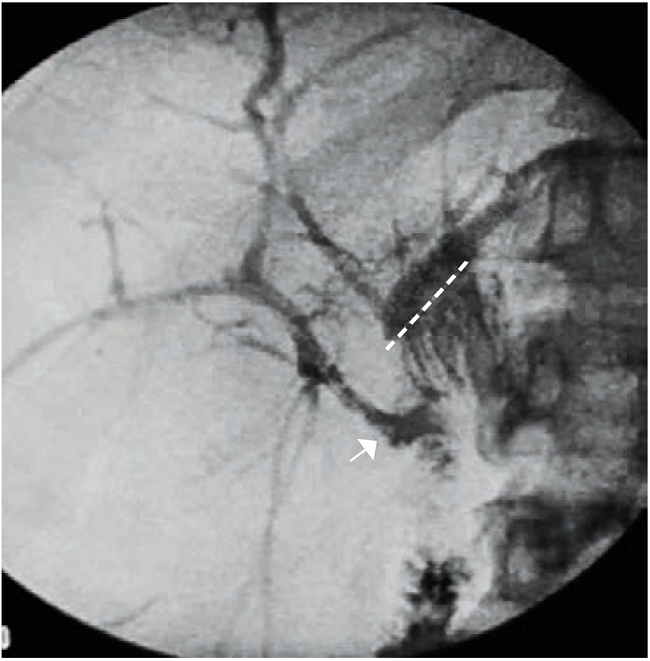

La evolución posoperatoria fue satisfactoria y se le dio egreso a la paciente al tercer día de la intervención. En la colangiografía de control a los tres meses, se demostró la permeabilidad de la anastomosis (figura 2). A los doce meses de seguimiento, la paciente se mantiene en condiciones estables, bajo un esquema de control ambulatorio anual (examen clínico, pruebas de laboratorio y ultrasonido hepático).

Además, en el presente caso, se practicó una colangiografía percutánea intraoperatoria y se colocó un catéter en el conducto hepático derecho, lo cual facilitó localizar esta estructura anatómica y exponerla durante el acto quirúrgico, además de permitir el control radiológico posoperatorio (figura 2). En relación con esto, y como resultado de la disposición del conducto hepático derecho dentro del parénquima hepático, el ultrasonido transoperatorio o la colocación de un catéter en su interior proporcionan información adicional para localizar esta estructura anatómica, lo cual permite acortar los tiempos quirúrgicos y mejorar los resultados posoperatorios. Este último punto plantea un interesante tema de discusión, según lo propone Pekolj en su editorial recientemente publicada 20.